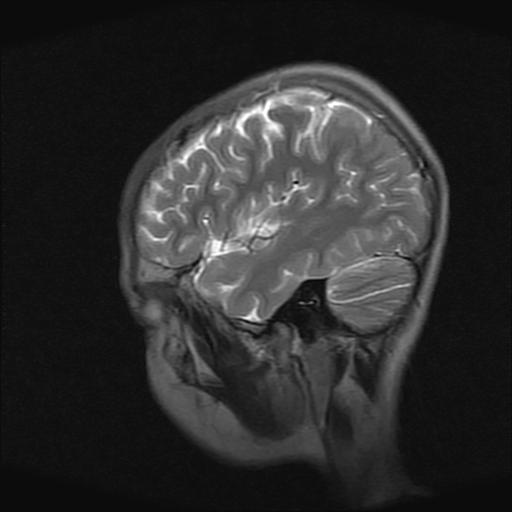

9岁女孩,三岁时诊断为癫痫,一直服丙戊酸钠,现患者一般情况良好,家长复查核磁片,看能否停药..

巨脑回